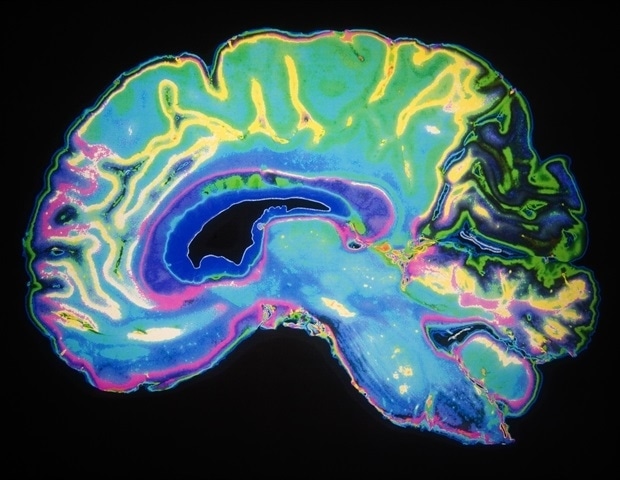

קשרי תאי מוח נחלשו במהלך המחצית הראשונה של השינה, כך עולה ממחקר

במהלך השינה, המוח מחליש את הקשרים החדשים בין נוירונים שנוצרו בזמן ערות – אך רק במהלך המחצית הראשונה של שנת

במהלך השינה, המוח מחליש את הקשרים החדשים בין נוירונים שנוצרו בזמן ערות – אך רק במהלך המחצית הראשונה של שנת